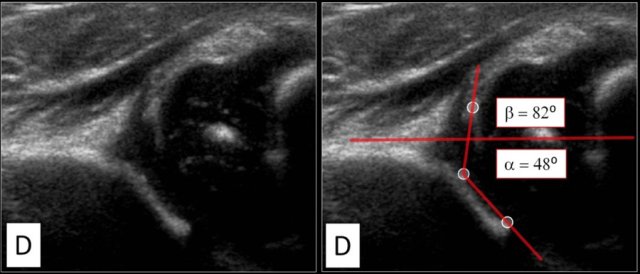

First three points of interest need to be indentified in the image:

1. Centre of labrum

2. Lower limb of the iliac bone (=Undersurface of the medial border of the acetabulum where the iliac bone meets the triradiate cartilage)

3. Bony rim of acetabulum. When the bony rim is angular this point is easily recognized. When rounded this point is defined as the point where the concavity of the bony acetabular roof changes into the convexity of the ilium

In this video you'll see proper measurement after placement of the three points of interest.

When you perform the ultrasound examination, make sure that these three points can be identified on the image.